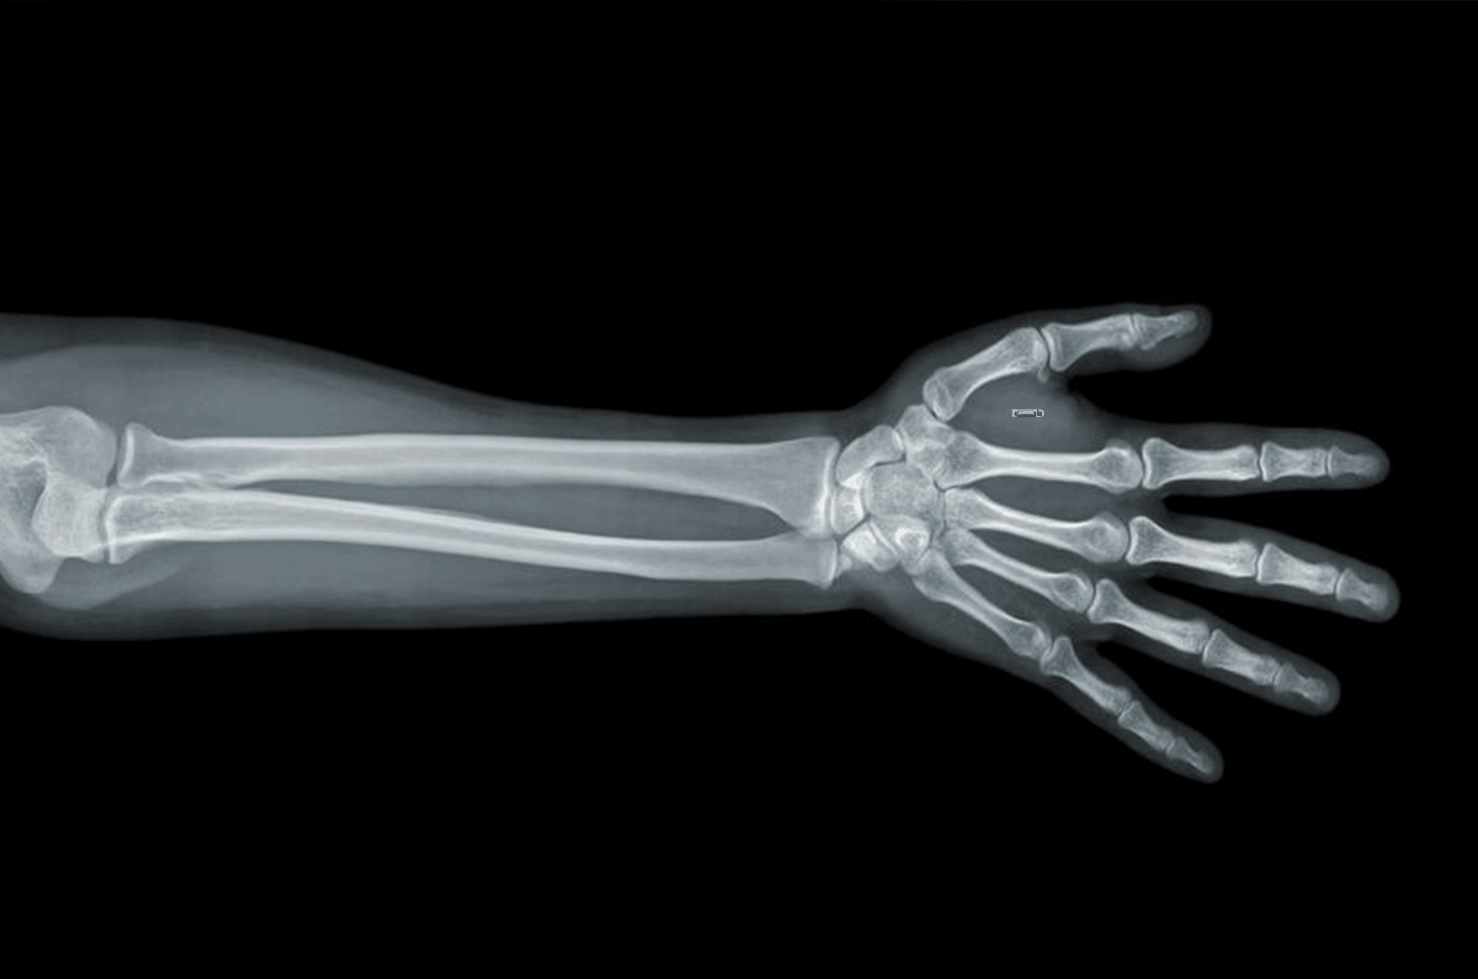

Перелом Коллеса

Перелом Коллеса — это перелом одной или обеих костей предплечья чуть выше запястья. Этот тип перелома чаще всего возникает, когда человек пытается поймать себя при падении вперед, вытягивая руки и руки, чтобы уменьшить воздействие удара о землю.

Симптомы перелома Коллеса включают:- Боль и отек чуть выше запястья

- Неспособность держать или поднимать тяжелые предметы

Лечение переломов Коллеса обычно включает иммобилизацию запястья и руки гипсовой повязкой.Если перелом более серьезный, может потребоваться хирургическое вмешательство, включающее штифты или винты для удержания костей вместе.

Перелом дистального отдела лучевой кости

Лучевая и локтевая кости — две кости предплечья. Перелом дистального конца лучевой кости, конца кости возле запястья, является наиболее часто ломаемой костью запястья.

Падение на вытянутую руку обычно вызывает этот тип перелома.

Симптомы перелома дистального отдела лучевой кости включают:

- Запястье выглядит искривленным и деформированным

- Боль, болезненность и припухлость в запястье

- Трудно двигать запястьем

Варианты лечения переломов дистального отдела лучевой кости зависят от тяжести перелома.Если концы костей выровнены, будет применена скоба. Если перелом со смещением, врачу может потребоваться выровнять концы костей, а затем наложить скобу, чтобы обездвижить запястье, пока кости срастаются. Наши ручные врачи в Эмори обсудят наилучший вариант лечения перелома дистального отдела лучевой кости.